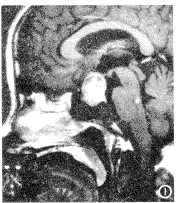

19例垂体腺瘤在MRI矢状面及冠状面均可见蝶鞍内肿块,肿块向上突入鞍上池,蝶鞍扩大,鞍背变薄及破坏。本组14例矢状面清楚显示视交叉受压上抬;冠状面显示1例压迫视交叉左侧及1例显示视交叉偏右侧受压上抬;3例视交叉受压已显示不清(图1)。

图1 垂体腺瘤,视交叉受压上抬。